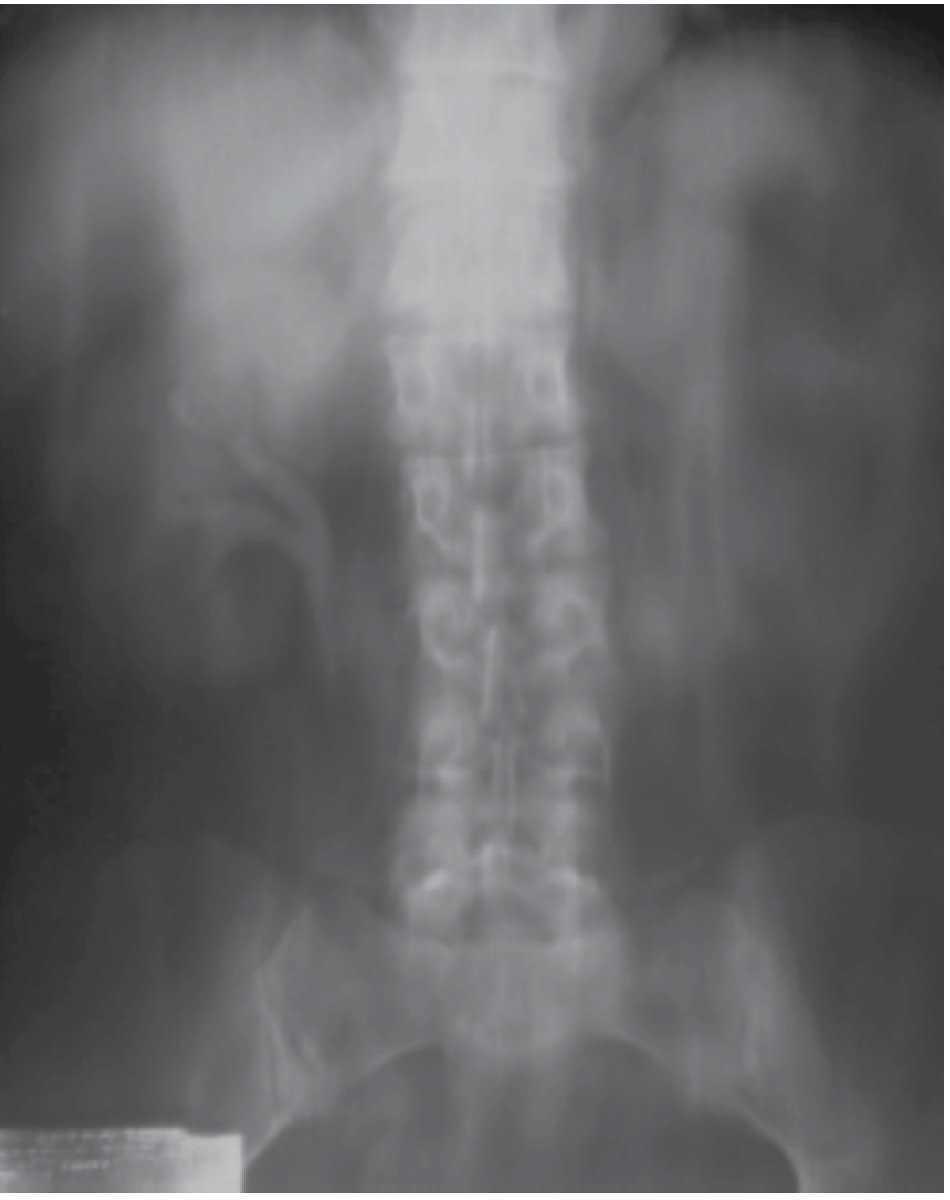

A cinco años de la primera cirugía, la paciente se encuentra actualmente en buenas condiciones generales. Se realizaron estudios de laboratorio con urea y creatinina conservada, pruebas de función hepáticas sin alteraciones, biometría hemática y ES normales, EGO sin hematuria y las citologías urinarias seriadas se han reportado como negativas. Estudios de imagen incluidos radiografía de tórax y tomografía sin datos patológicos o anomalías que comentar.

En la USG presenta el riñón con cambios degenerativos crónicos, vejiga de bordes regulares sin engrosamiento de sus paredes, anecogénica en su interior. Gamagrama óseo: proceso osteoarticular degenerativo e inflamatorio articular, negativo a malignidad.

Y su última cistoscopia de control reporta cicatriz quirúrgica en hemitrígono izquierdo. Meato ureteral derecho eyaculando orina normal, vejiga con trabeculaciones grado II, no se aprecian sitios de sangrado, ni frondas tumorales. La ureteroscopía flexible de control sin evidencia de recidiva tumoral.